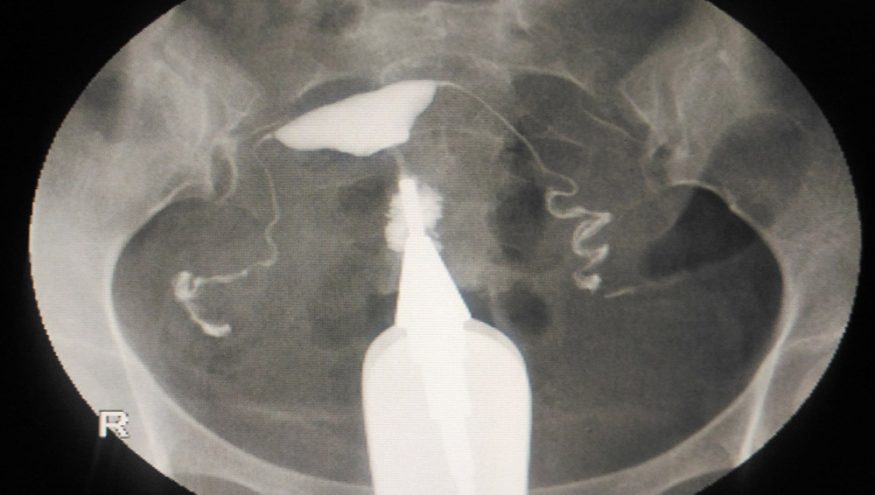

Histerosalpingografi normal olarak radyoloji bölümünde çekilir ve yaklaşık 15 dakikada tamamlanır. Radyografinin çekilmesi çok çabuk gerçekleşir ama aletlerin yerlerine yerleştirilmesi gibi gerekli hazırlıklar, daha fazla zaman alır. Histerosalpingofrafide kullanılan farklı aletler vardır ama ilk basamak, daima aynıdır – bir spekulum yerleştirilerek rahim boynu, genellikle iyot çözeltisiyle dezenfekte edilir. Daha sonra serviks, aynı pozisyonda kalmasını sağlamak amacıyla bir çift küçük pensle tutulur. Bu sırada hasta, bir iğne batıyormuş hissine kapılabilir. Daha sonra diğer bir aletle yağ- veya su-bazlı bir boya (kontrast sıvı), serviksten girilerek rahim boşluğuna verilir. Basınç artırıldığında boya, fallop tüplerinden geçerek sonunda karın boşluğuna girer. Kontrast maddenin bu şekilde ilerlemesi, uterus boşluğunun biçiminin ve yapısının incelenmesine, ayrıca fallop tüplerinin açık olup olmadığının değerlendirilmesine yardım eder. Kontrast sıvının izlediği yolun aşama aşama çok sayıda radyografisi çekilir; sonuçlar, renkli kontrast sıvı rahim boşluğunu doldurup fallop tüplerinin ucundan karın boşluğuna doğru taştığı ve tüplerin açık olduğunu (veya olmadığını) doğruladığı için ‘dolma ve taşma’ olarak adlandırılır. Bu test sırasında tüpler basınç altında gerildiğinden bazen, açık oldukları halde ‘tıkalı’ gözükebilir. Kesin sonuçlar bu nedenle yalnızca, böyle bir gerilme olmadığı sürece elde edilebilir. Histerosalpingogramda anormallikler varsa daha sonra, bu sonuçları doğrulamak veya reddetmek amacıyla genellikle görsel bir operasyon yapılır.